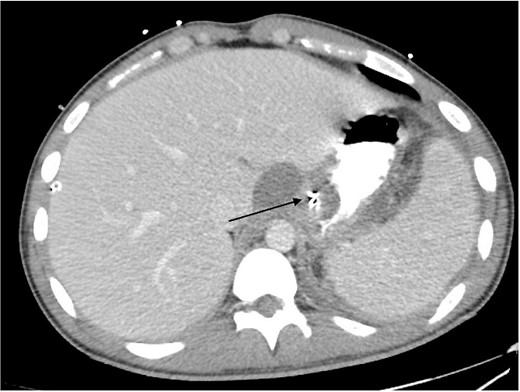

2L of pus was evacuated during laparoscopy, and it was converted to open due to limited views. At this stage, there was no obvious perforation. The entire colon was inspected, following splenic flexure and caecal mobilization. On inspection of the stomach, the wrap was intact with an unremarkable leak test. The decision was made to proceed with gastroscopy, whereby a 3 mm pinhole defect was seen at the GOJ at the 9 o’clock position, as shown in Fig. 2. Three haemostatic Cook Medical Instinct clips were placed, from distal to proximal, ensuring there was stable apposition of the perforated mucosa prior to deploying, as demonstrated in Fig. 3. Following this, the NGT was re-inserted under vision. The midline laparotomy was partially closed and Abthera dressing placed. The patient was taken to ICU intubated, with definitive closure performed 48 h later.

Gastroscopic image demonstrating the successful application of haemostatic clips at the site of perforation (arrow).